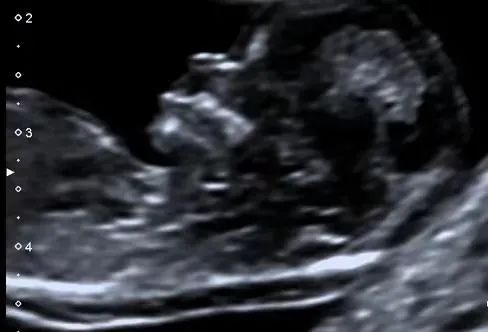

近日,一位准妈妈,27岁,2022年曾接受霍奇金淋巴瘤治疗,目前怀孕14周,来到我院超声科进行早孕期胎儿结构筛查。此次检查中,胎儿的颈项透明层(NT)厚度为1.7mm,处于正常范围。然而,超声检查发现胎儿心脏存在室间隔膜周部缺损,对此情况建议孕妇前往产前诊断门诊进行咨询。这是我院超声科首次成功完成的早孕期胎儿结构筛查,同时也是池州市首例此类检查。

随着超声诊断仪器性能的不断提高以及超声医师诊断经验的日益丰富,早孕期胎儿检查的深度和细致程度也在不断提高。在早孕期,我们不仅可以筛查与胎儿非整倍体染色体异常相关的软指标,还可以对胎儿的解剖结构进行检查,从而提前发现某些胎儿结构畸形,实现早期诊断和早期处理。